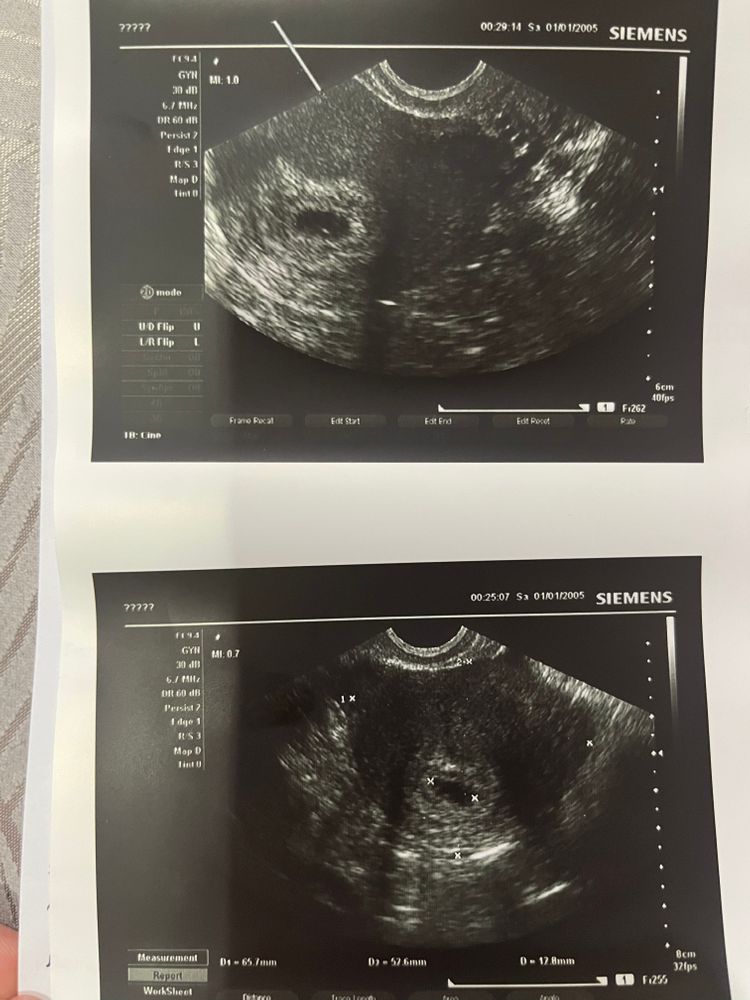

Алия, добрый вечер. Сходила, но как то больше вопросов, чем ответов. Через неделю повторно нужно будет сделать. Изображение Изображение

Fox и, это значит плодное яйцо в матке, но эмбрион пока не видят. Такое бывает на малых сроках. Пусть всё у вас сложится наилучшим образом🙏